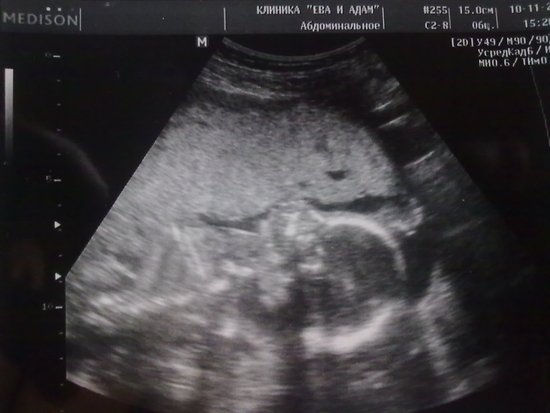

Так мы и хихикали с узисткой все это время, пока пытались поймать эту красотулю для фото, я не суеверная, кому интересно - вот что у нас с мужем получилось:)